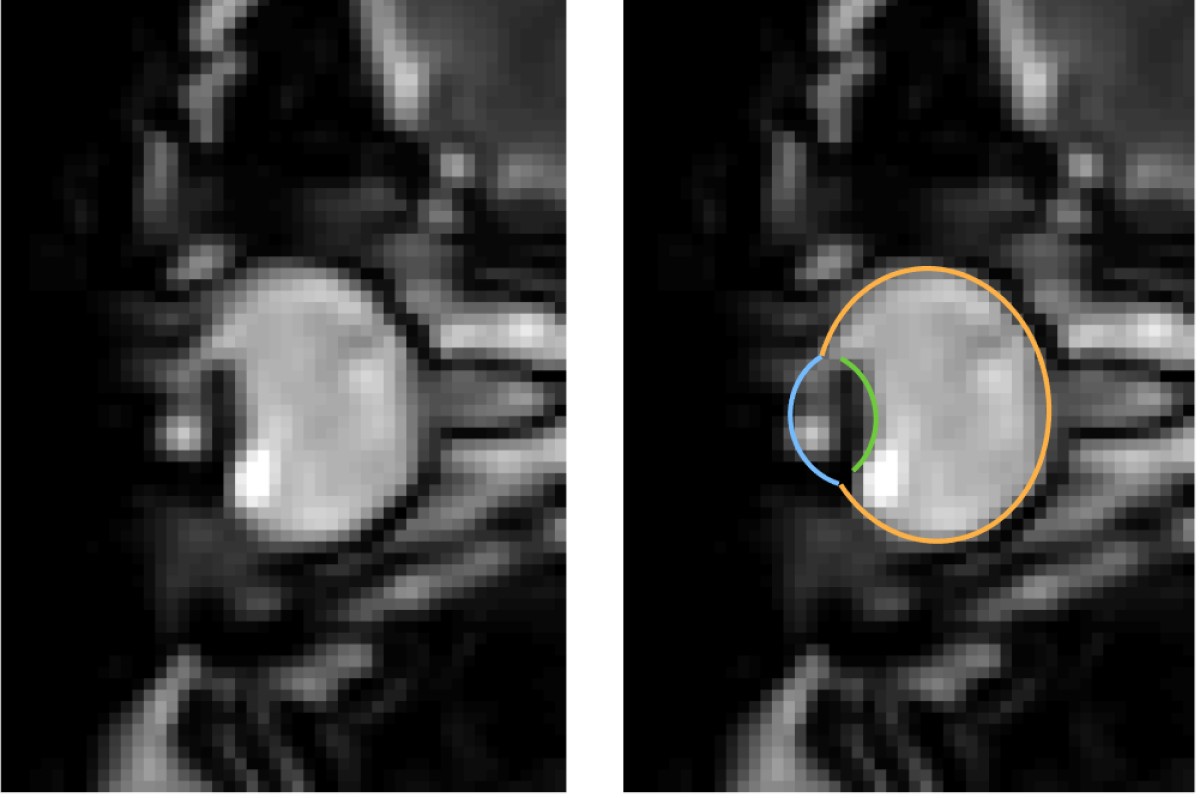

MRI images of eye movements during blinking: The eye is pulled back into the eye socket. The left image shows only the dynamic MRI data, the right image additionally shows the segmentation of the eye by the MREyeTrack. The photo corner consisting of six images shows the eye movement.© WWU - Johannes Kirchner

Eye movements are typically measured using eye-trackers, which are high speed cameras that film pupil position.” We were able to develop a method that captures eye movements in unprecedented temporal resolution using real-time MRI. Using this new method, we could show that the whole eyeball is being pulled back into the eye socket during a blink“, explains author Johannes Kirchner, research assistant at the Institute of Psychology at Münster University. The scientists from the University of Münster developed the method with co-author Prof. Tamara Watson from Western Sydney University.

MRI is a relatively slow procedure, the temporal resolution usually ranges between seconds or minutes. Eye movements on the other hand are fast and typically last only a few dozen milliseconds. Recent technological advances allowed the recording of 2-D MR images at a resolution of up to 20 milliseconds. Those ultrafast MR sequences were initially developed for cardiac imaging and haven’t been applied to the recording of eye movements. “We could reach a temporal resolution of 35 milliseconds. Total scan duration of only a few minutes already leads to the acquisition of over 10000 images. For actual eye-tracking, a fully automatic segmentation algorithm to analyse these images was needed”, explains co-author Prof. Markus Lappe, professor for cognitive neuroscience at the Institute of Psychology at the University of Münster. “With ‘MREyeTrack’ we have developed such a segmentation algorithm, which allows the fully-automated analysis of eye position and orientation in every single image.”